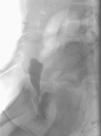

Case 2. Girl, 9 years of age with diurnal incontinence and lower UTIs. She had received previous treatment with oxybutynin for suspected overactive bladder and showed no response to it. Uroflowmetry with electromyography revealed uncoordinated voiding, leading to the initiation of a biofeedback programme that had poor results despite improvement in the uroflowmetry tracings. It was decided to perform VCUG, which revealed VR (Fig. 2). Urotherapy specific to VR was initiated. Six months after starting treatment, the patient stopped having urine leaks.